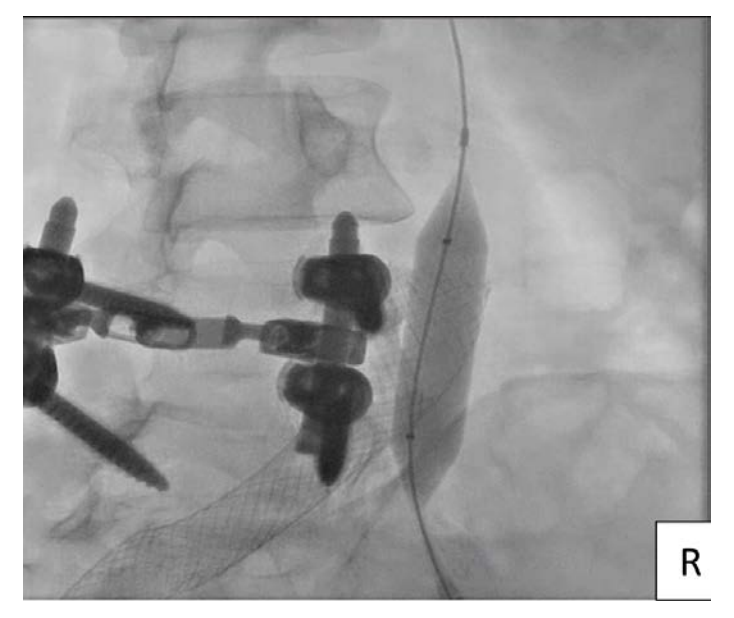

The patient was placed in a prone position and access via the ipsilateral right popliteal vein was obtained. A Destination sheath (Terumo) was advanced over a Wholey wire (Medtronic) to the area of the thrombus (Figure 1). The wire was advanced through the occluded thrombus in the right CIV, with care taken in order to avoid entering through the contralateral stent struts that extended into the IVC. Intravascular ultrasound (IVUS) was used to confirm the location of the wire between the wall of the IVC and the Wallstent (Figure 2).